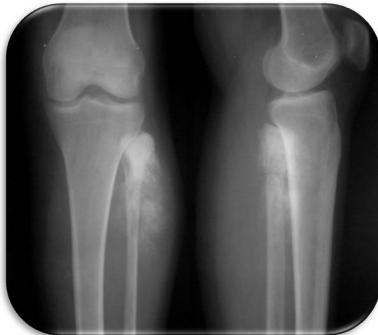

Aneurysmal Bone Cyst

site: Distal tibial

size: Involving most of distal part

matrix: Cortical expansion, radiolucent matrix, well defined, narrow zone of transition

soft tissue involvement: no peristeal reaction